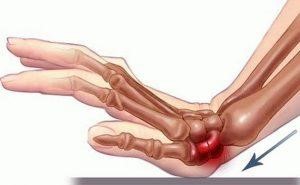

شکستگی اسمیت؛ معکوس کالیس و پرخطرتر

در این شکستگی قطعه شکسته شده به طرف کف دست منحرف می‌شود. مکانیسم ایجاد آن زمین خوردن روی پشت دست است. به دلیل بی‌ثباتی بیشتر این شکستگی نسبت به کالیس، احتمال نیاز به جراحی بالاتر است. اگر جااندازی بسته موفق نباشد یا قطعات دوباره جابجا شوند، عمل جراحی برای تثبیت با پیچ و پلاک انجام می‌شود.